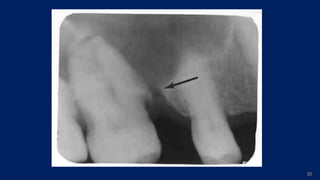

Oro-antral communication

(It is a pathologic tract that connects the oral cavity to the maxillary sinus.)

•Maxillary sinus perforation occurs occasionally during the extraction of a

maxillary tooth, and it may be a cause of maxillary sinusitis or oro- antral

fistula.

•Patient complained of regurgitation of food through the nose while eating.

Clinical Considerations:

•Oro-antral communication and oro-antral fistula

•The chances of creating an oro-antral fistula in patient less than 15 yrs are

comparatively lesser than in adults due to incomplete development of sinus.

•The distance between apical end of maxillary posterior teeth and floor of

sinus is approximately 1-1.2 cm. In some cases the gap may be still lesser.

 Root which is most close to the sinus is “palatal root of maxillary

1st molar

 Followed by :

◦ 1st premolar

◦ 2nd premolar

◦ 2nd molar